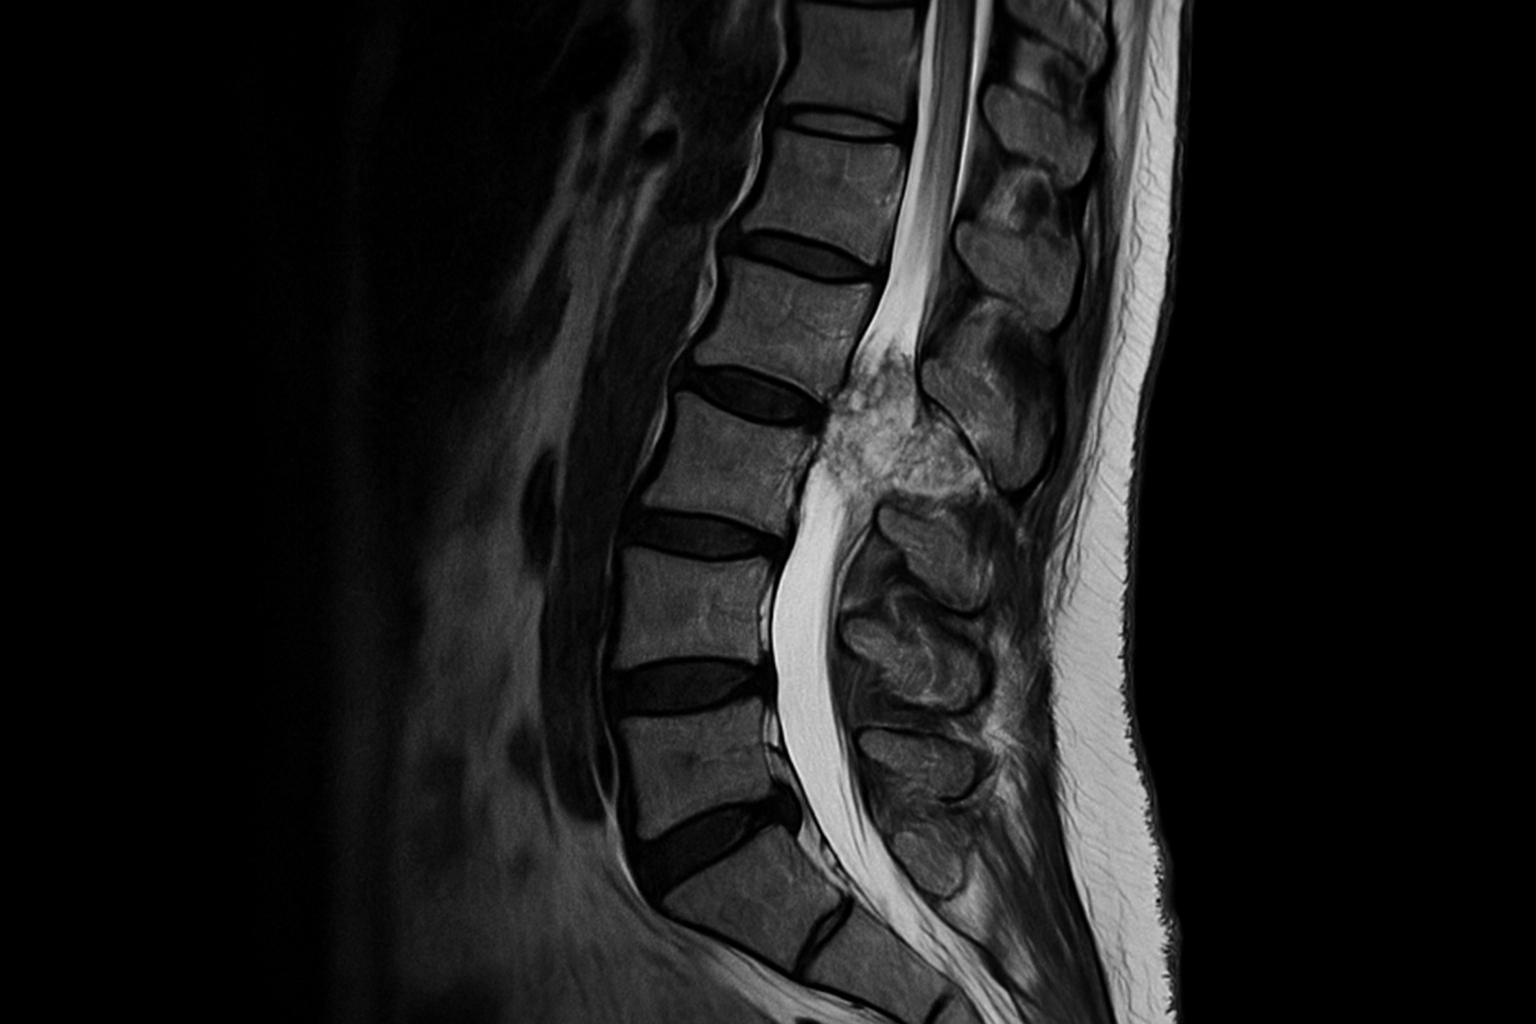

Spinal cord compression is a devastating complication of cancer. Prompt recognition and treatment offer the best chance of limiting its long-term consequences. In this lecture, Dr Markides will explore the emergency physician’s vital role in the chain of care. Following a brief review of the pathophysiology of metastatic spinal cord compression, we will examine its clinical presentation and diagnostic work-up. As treatment requires a multidisciplinary approach, the discussion will highlight how this process begins in the emergency department.